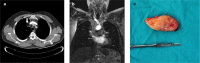

Primary Intravascular Lipoma of the Superior Vena Cava